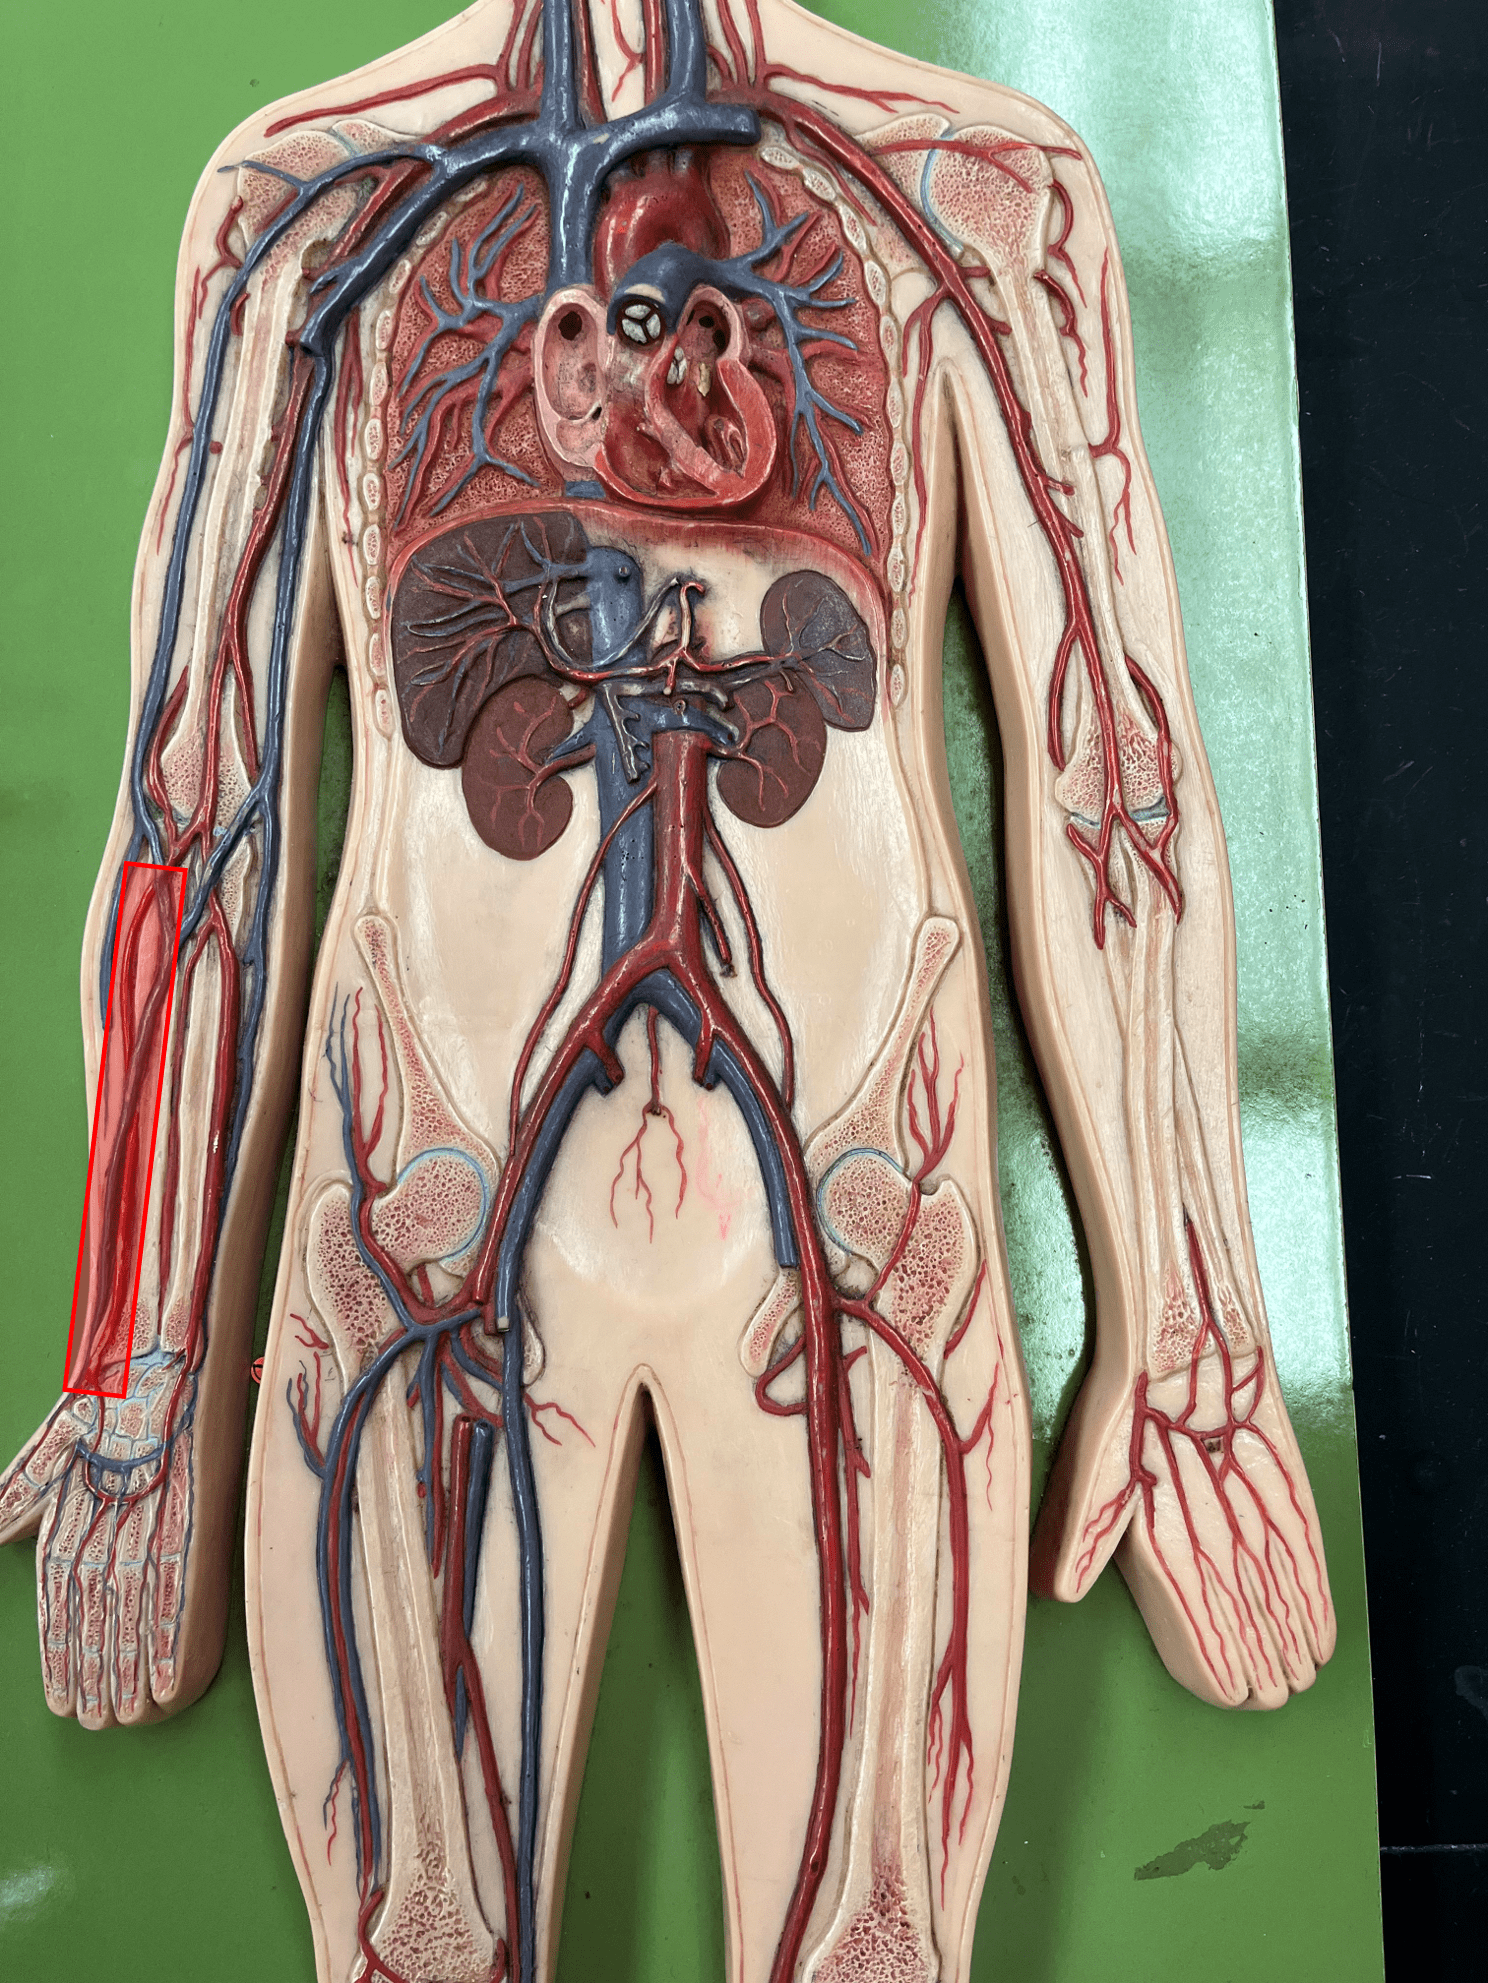

• Found between the tunica media and tunica interna.

• Allows the lumen of a blood vessel to stretch.

10

New cards

tunica interna

• The innermost layer of an artery.

• Consists of an inner endothelium and an outer basement membrane.

• Also known as the tunica intima.

• Consists of an inner endothelium and an outer basement membrane.

• Also known as the tunica intima.